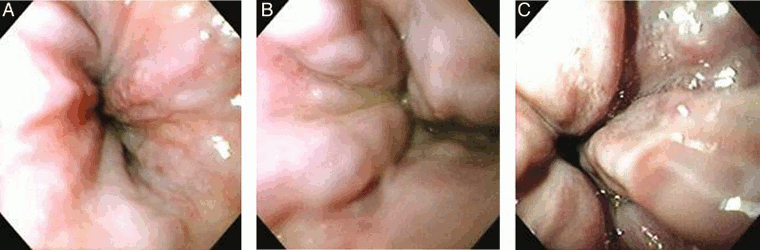

[Figure caption and citation for the preceding image starts]: (A) Grade I esophageal varices. These collapse to inflation of the esophagus with air. (B) Grade II esophageal varices. These are varices between grades 1 and 3. (C) Grade III esophageal varices. These are large enough to occlude the lumenTripathi D et al. Gut 2015;64:1680-704; used with permission [Citation ends].